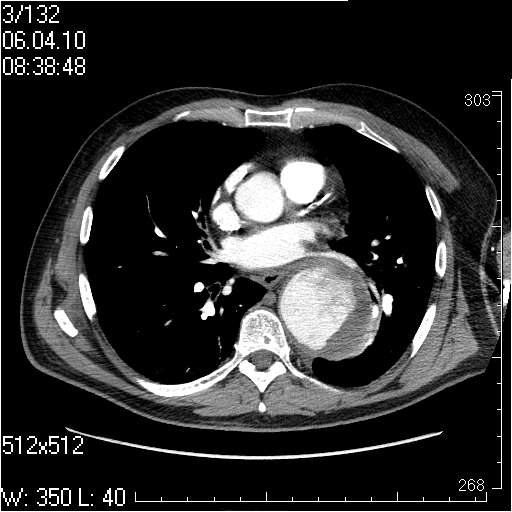

Грудной отдел аорты

Пожилой мужчина, жалоб в настоящее время не предъявляет.